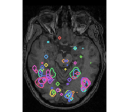

face

vs house

TV-l1

Graph-net

Social sparsity

Finally, an important aspect of the brain decoders is whether they segment well the brain regions that support the decoding. Such a question is hard to validate, yet there is evidence that TV- is a good approach [5]. Fig. 2 displays the decoder maps for the object-recognition tasks. For these tasks, we expect prediction to be driven by the functional areas of the visual cortex [27]. Indeed, the maps outline regions in known visual areas. The graph-net maps are much more scattered and less structured than the others. Conversely, the social sparsity maps are sparser and outline a smaller number of clusters.